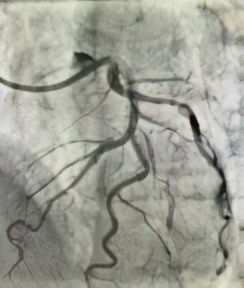

杨某,男,68岁,“因反复胸闷一周”入院,入院后行冠脉造影术,透视下见冠脉严重弥漫性钙化,右冠中段闭塞;前降支近段到中段严重95-99%弥漫性狭窄,病变处发出粗大第二对角支,第二对角支开口到近段95-99%弥漫性狭窄,属于真性分叉病变伴严重钙化;回旋支近段80%弥漫性狭窄,发出丰富侧枝循环供应右冠。患者命悬一线!刘杰主任率先对前降支分叉病变预处理后,在OCT指导下完成了分叉支架手术(culottes),术后OCT结果显示分叉支架贴壁良好,术后患者胸闷立即改善。

术后